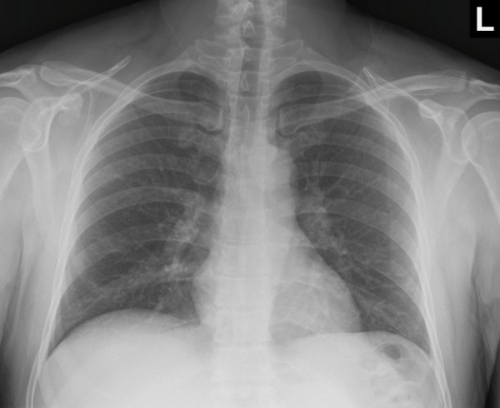

Tool to train medical student's eyes as to what a normal chest x-ray looks like, with over 500 consecutive normal images.